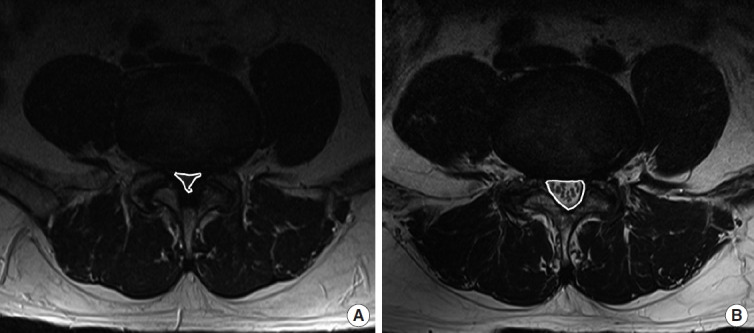

Methods: This retrospective study included 86 patients, divided into ULBD-UBE (n=34), STL (n=24), and MIS-TLIF (n=28) groups. We evaluated demographics and perioperative factors and assessed clinical outcomes using the visual analogue scale (VAS), Oswestry Disability Index (ODI), and neurogenic intermittent claudication (NIC). Radiological parameters assessed included lumbar lordosis, L4S1 Cobb angle (L4S1), T12S1 Cobb angle (T12S1), increased cross-sectional dural area (CSA), dynamic angulation (DA), dynamic slip (DS), and development of postoperative instability.

Results: The ULBD-UBE group showed a significantly shorter hospital stay duration and operation time and reduced blood loss than the other groups (p<0.001). ULBD-UBE group showed a trend towards greater VAS and ODI improvement at 1 month and postoperative NIC symptom relief. Radiologically, MIS-TLIF group exhibited lower postoperative DA and DS (p<0.001), indicating higher postoperative stability. Postoperative instability was lower in the ULBD-UBE group (2.9%) than in the STL group (16.7%) and similar to the MIS-TLIF group (0.0%) (p=0.028). The CSA was highest in the MIS-TLIF group (295.5%) compared to that in the other groups (ULBD-UBE, 216.3%; STL, 245.2%) (p<0.001).